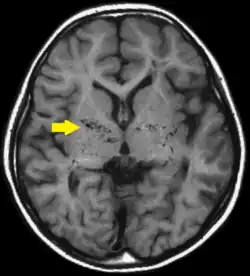

![]() | |

T1-weighted MR image of moyamoya disease. Flow void in the basal ganglia is indicated by the arrow. | |